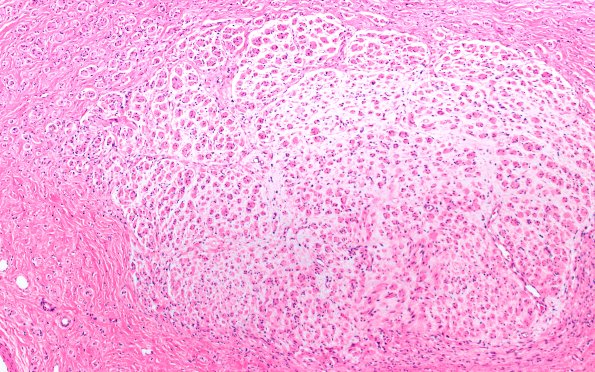

6A2 Neuroma (Case 6) PROX H&E 10X 1

A higher magnification of one fascicle giving rise to mini-fascicles. (H&E)